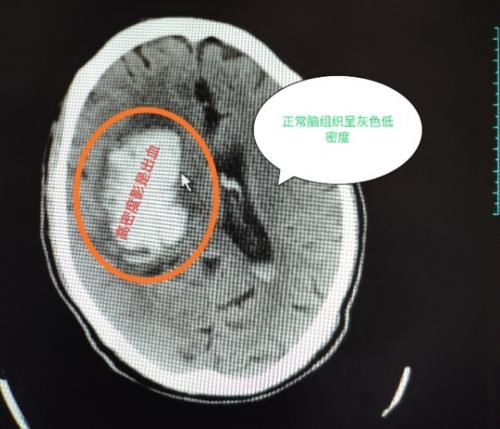

她因为和别人吵架导致晕厥,随后拨打我们医院120急救中心电话,送入我们医院,别看这位患者那么瘦,他已经有高血压5年多了,根据家属交代平时也不怎么爱吃药,脾气比较急,当时我就考虑脑出血或者脑梗死,给患者简单的生命体征评估后,当时测量患者血压高达210/126mmHg,立即给予患者行急诊头颅CT平扫,下图是头CT影像结果

CT图像看到右侧大脑大片高密度影,提示脑出血,后转入我院神经外科ICU住院治疗。